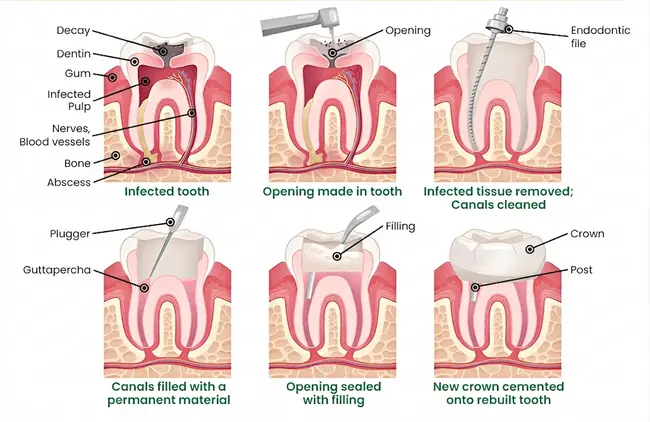

A root canal is a precise procedure to take out inflamed or infected pulp — the soft inner tissue containing nerves and blood vessels — deep inside the tooth.

Dr. Soyfer then cleans each root canal and shapes it to leave the best opening for disinfecting, where she kills any bacteria in the canals and fills them with a safe, biocompatible material that seals them off.

The procedure is concluded with a strong crown or filling, which restores the tooth to its inherent strength and function. These days, thanks to precise toolwork, digital imaging and effective local anesthesia, most patients visiting our Arlington office are surprised at how extremely comfortable the procedure is — often reporting that for them the greatest advantage of their experience was finding quick relief from chronic pain.

Thorough Analysis

Involves a focused examination and high-quality digital imaging to delineate the infection and help you formulate a personalized plan with upfront costs.

Gentle Numbing

Local anesthetic is administered to ensure the area under treatment is very comfortable.

Cleaning as a precise work

The infected pulp is removed, canals shaped and disinfected from all bacteria.

Seal securely

Canals are filled with a durable, biocompatible material and temporarily protected.

Final Restoration

Generally performed with a custom crown that integrates seamlessly and fortifies the tooth for daily usage.

The majority of root canals are completed quickly over the space of one or two appointments, typically about 1–2 hours long (front teeth are simpler; molars with multiple canals may require more work).